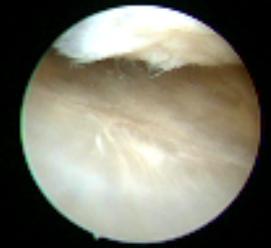

Avendo iniziato nel 2007 i risultati sono ormai molto conosciuti e la rigenerazione è stata studiata nei minimi dettagli: sono stati eseguiti molti prelievi per esaminare il nuovo tessuto che si è formato e gli esami istologici hanno confermato essere una cartilagine normale.

I pazienti hanno avuto un grande miglioramento con la scomparsa dei disturbi provocati dal danno cartilagineo ed un ritorno alle normali attività.